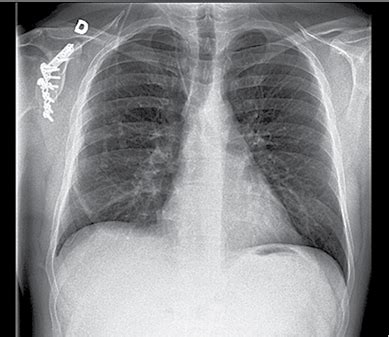

Kitas atvejis apibūdina 46 metų moterį, kuri buvo skubiai pristatyta į priėmimo skyrių su centrine dusulio, krūtinės skausmo ir dvipusio kaklo patinimo istorija. Valandą prieš tai jai buvo atlikta dešiniojo apatinio antrojo krūminio danties šalinimo procedūra vietinėje nejautroje. Jos bendra būklė buvo gera. Apžiūra parodė dvipusį kaklo patinimą ir vidurinės linijos trachėją, su traškėjimu liečiant, rodantį gilią odos emfizemą. Krūtinės rentgenograma parodė difuzinę poodinę emfizemą, pneumomediastino ir dalinį dešinįjį pneumotoraksą.

- Krūtinės ląstos rentgenograma: Tai pirminis diagnostikos metodas. Ji gali parodyti poodinę emfizemą kaklo ir klakulinėse srityse, taip pat pneumomediastino. Tačiau kartais mažos oro kiekiai gali būti nepastebimi.

- Krūtinės ląstos kompiuterinė tomografija (KT): KT laikoma "aukso standartu" diagnozuojant pneumomediastino, nes ji gali aptikti net mažus oro kiekius, kurie nepastebimi rentgenogramoje. Tai taip pat leidžia atmesti kitas būkles, tokias kaip mediastinitas, laisvas skystis ar stemplės plyšimas.